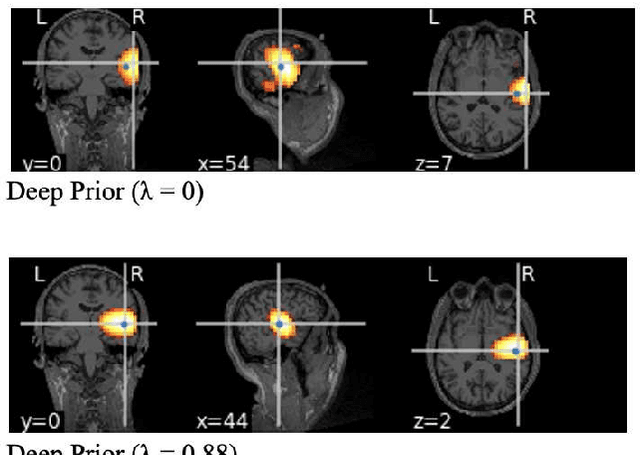

Abstract:This paper proposes a novel neuronal current source localization method based on Deep Prior that represents a more complicated prior distribution of current source using convolutional networks. Deep Prior has been suggested as a means of an unsupervised learning approach that does not require learning using training data, and randomly-initialized neural networks are used to update a source location using a single observation. In our previous work, a Deep-Prior-based current source localization method in the brain has been proposed but the performance was not almost the same as those of conventional approaches, such as sLORETA. In order to improve the Deep-Prior-based approach, in this paper, a depth weight of the current source is introduced for Deep Prior, where depth weighting amounts to assigning more penalty to the superficial currents. Its effectiveness is confirmed by experiments of current source estimation on simulated MEG data.